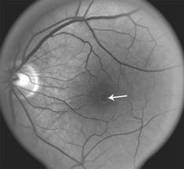

Smoke stack appearance

Ink blot appearance